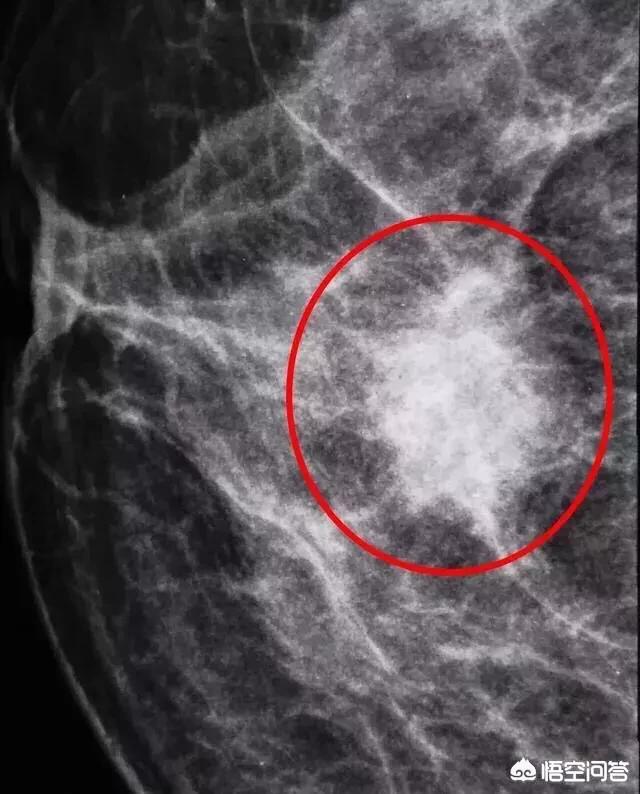

5级:高度怀疑恶性。影像上有95%的可能性考虑乳腺癌。比如乳腺钼靶看到沙粒样钙化。比如病灶有边界不清,有毛刺、分叶,淋巴结肿大等征象。

如图,我看到这样的钼靶图像,直接下5级,病灶分叶,毛刺明显,有95%的可能性是乳腺癌。病理证实是乳腺癌。